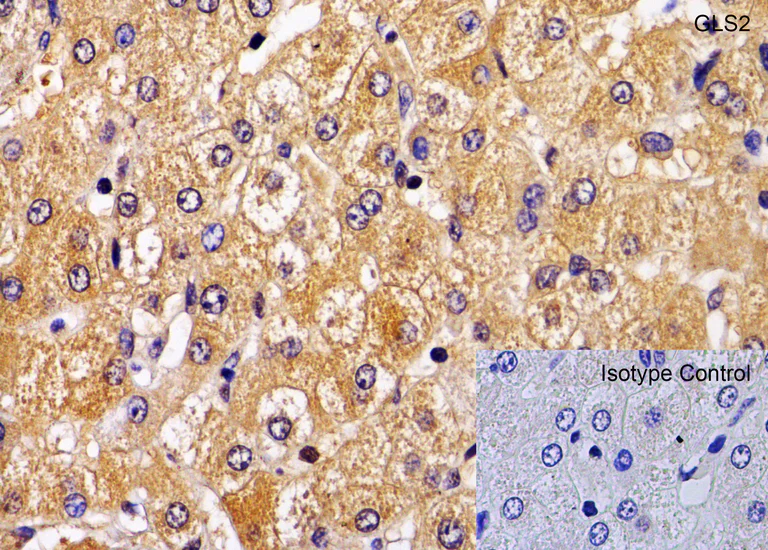

Immunohistochemistry (Formalin/PFA-fixed paraffin-embedded sections) - Anti-GLS2 antibody (AB113509)

Immunohistochemical analysis of paraffin-embedded human liver tissue labelling GLS2 with ab113509 at 1 μg/ml. Tissue was fixed with formaldehyde and blocked with 10% serum for 1 h at RT; antigen retrieval was by heat mediation with a citrate buffer (pH6). Samples were incubated with primary antibody overnight at 4°C. Goat anti-rabbit IgG H&L (HRP) at 1/250 was used as secondary. Counter stained with Hematoxylin.